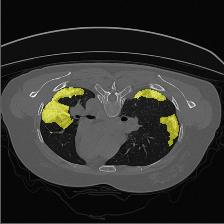

Medical image segmentation is one of the most fundamental tasks concerning medical information analysis. Various solutions have been proposed so far, including many deep learning-based techniques, such as U-Net, FC-DenseNet, etc. However, high-precision medical image segmentation remains a highly challenging task due to the existence of inherent magnification and distortion in medical images as well as the presence of lesions with similar density to normal tissues. In this paper, we propose TFCNs (Transformers for Fully Convolutional denseNets) to tackle the problem by introducing ResLinear-Transformer (RL-Transformer) and Convolutional Linear Attention Block (CLAB) to FC-DenseNet. TFCNs is not only able to utilize more latent information from the CT images for feature extraction, but also can capture and disseminate semantic features and filter non-semantic features more effectively through the CLAB module. Our experimental results show that TFCNs can achieve state-of-the-art performance with dice scores of 83.72\% on the Synapse dataset. In addition, we evaluate the robustness of TFCNs for lesion area effects on the COVID-19 public datasets. The Python code will be made publicly available on https://github.com/HUANGLIZI/TFCNs.